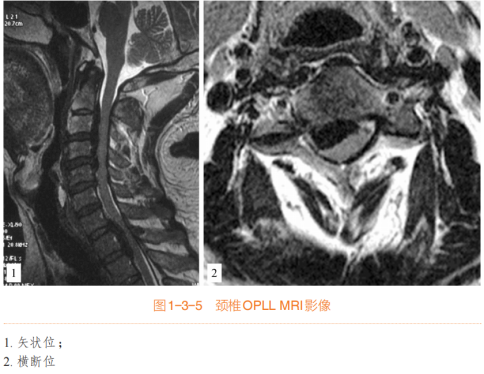

(一)颈椎后纵韧带骨化(OPLL)

骨化物位于椎体后缘,预计经椎间隙无法清除

骨化物累及1 ~ 4个节段(如有准备长节段钛板,亦可治疗长达5 ~ 6个节段的颈椎OPLL)

骨化物累及C2后方或T1后方的高低节段骨化

突出的局限型骨化,预计后路减压效果不佳

对于骨化范围>3个节段、椎管狭窄率>60%、骨化物厚度>5 mm的严重颈椎OPLL患者,直接切除骨化物具有相当难度和风险,手术术式的选择一直是一个争议,此类型患者行ACAF技术的优势更加明显。

(二)脊髓型颈椎病(CSM)

ACAF技术主要适用于合并椎管狭窄、存在椎体后方骨赘、颈椎曲度不良的多节段颈椎病患者;对于各种先天性、发育性及退变性颈椎椎管狭窄症,椎管前后径<12 mm,或Pavlov比值<0.75的病变优势明显。